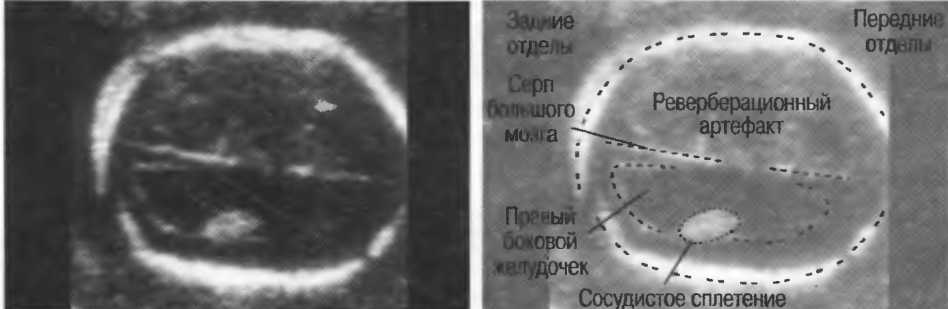

Рис.8б. Два аксиальных среза головки плода, развернутые на 180°. Перед проведением исследования ориентация изображения на экране должна быть проверена, как показано на рис. 8а.